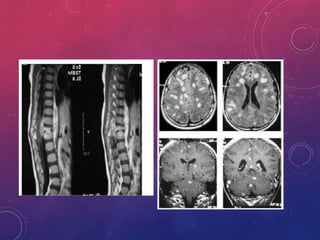

• En el Estadio I, parte de esos macrófagos alveolares pueden alcanzar

vía linfática los ganglios regionales, y desde aquí, vía hematógena, al

resto del organismo: riñones, epífisis de los huesos largos, cuerpos

vertebrales, meninges.

DIAGNÓSTICO: RADIOLOGÍA

• Es poco específico, pueden observarse cavernas, fibrosis,

infiltrados nódulos. La sensibilidad es menor de acuerdo

con el nivel de la inmunidad del paciente

• En un estudio prospectivo hecho en pacientes con VIH, el 8% de

los pacientes con TBC pulmonar tenían una RX de tórax normal.

• En otro estudio, el 32% de los pacientes con tuberculosis y

SIDA, tenían radiografías de tórax sin patrón sospechoso de

tuberculosis

• Cuando los CD4 eran menores de 200, la adenopatía mediastinal

fue más común, y la cavitación menos frecuente

• Se recomienda el esquema 2HRZE/10HR (12 meses) para

los casos de TB del SNC, inclusive en los afectados con

coinfección TB/VIH